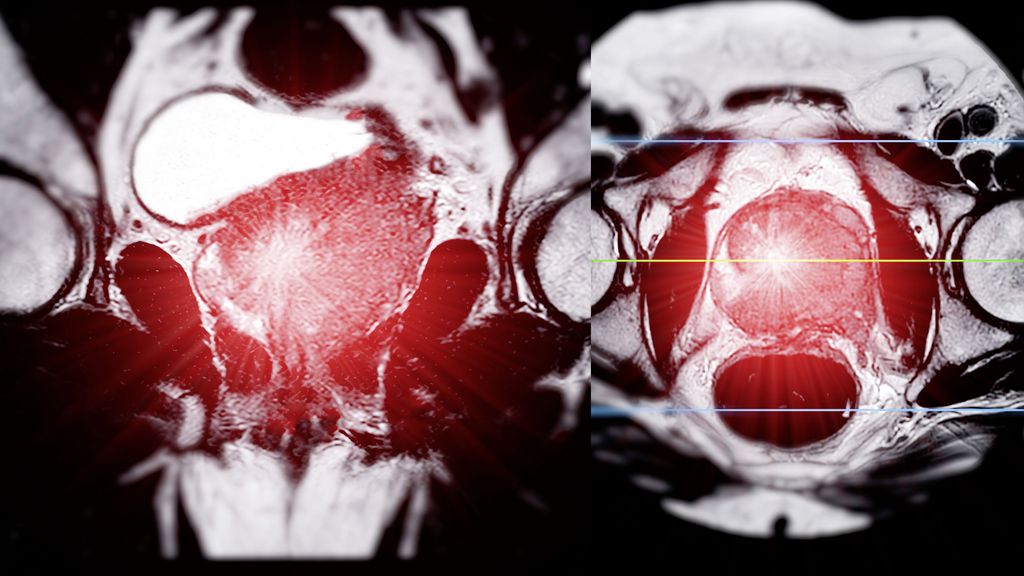

Les lésions hépatiques focales sont souvent détectées lors d’examens par TDM, IRM ou échographie, non seulement en gastroentérologie et en hépatologie, mais aussi en médecine interne et ...